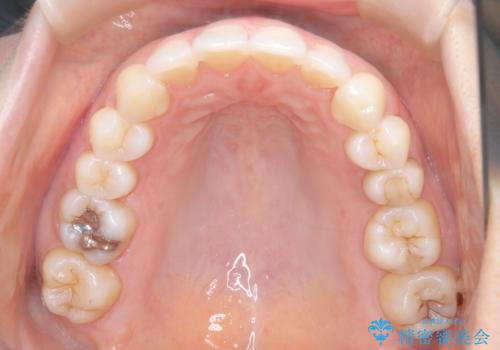

審美装置を用いたワイヤー矯正|非抜歯で歯の凸凹を改善

- 患者様は**歯の凸凹(叢生)**を気にされて来院されました。診査の結果、歯列のスペースが不足しているものの、抜歯をせずに改善できる状態でした。そこで、目立ちにくい審美装置(白いブラケットとホワイトワイヤー)を使用したワイヤー矯正を提案しました。歯列のアーチを広げながら、適宜IPR(歯の幅をわずかに調整する処置)を行い、非抜歯で自然な歯並びへと導く計画を立てました。

治療では、白いブラケットとホワイトワイヤーを使用し、矯正装置が目立ちにくいよう配慮しました。歯列を拡大しながら適切に歯を移動させ、IPRを併用することで、無理なくスペースを確保しました。見た目に配慮しながら、歯の凸凹をスムーズに整え、噛み合わせも改善。患者様からは「装置が思ったより目立たず、歯並びがきれいになって嬉しい」との声をいただきました。